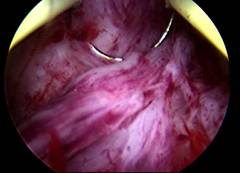

Normal Hysteroscopy

Hysteroscopic Cornual Cannulation